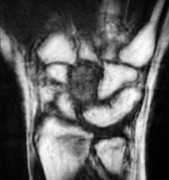

، أو لتقييم مدى تدهور العظم في حالات مثل مرض كينبوك. - التصوير بالرنين المغناطيسي (MRI): ممتاز لتقييم الأنسجة الرخوة مثل الأربطة، الأوتار، الأعصاب، والعضلات. يكشف عن التمزقات،

- الأشعة السينية (X-rays): هي الخطوة الأولى في تقييم الكسور، الخلوع، وتغيرات التهاب المفاصل. تساعد في تحديد مدى تدهور العظام والمسافات المفصلية. على سبيل المثال، تُظهر صور الأشعة السينية كسور السلاميات